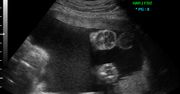

Zdjęcia płodu